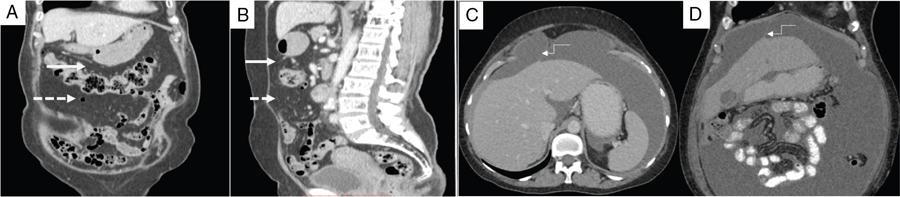

Shivsamb Jalkote, Slesha Bhalja, Disha Lokhandwala, Mansi Jantre, Karthik Ganesan Peritoneum is involved in a diverse group of primary as well as secondary pathologies ranging from the infective/inflammatory spectrum to malignancies. Peritoneal diseases are both common and potentially life threatening, and yet often get neglected in routine evaluation, due to the complex peritoneal anatomy and sometimes subtle imaging manifestations. The radiologist forms an integral part of the multidisciplinary team dealing with peritoneal pathologies and hence, having a lucid understanding of peritoneal anatomy, pathways of disease spread and different treatment options is paramount for an accurate radiological analysis. All three major serosal cavities (pleural, pericardial and peritoneal) of the body are derived from a single coelomic cavity, which is lined by a continuous mesothelium. At 2 weeks of gestational age, during the gastrulation stage, the embryo is a trilaminar disc, composed of the endoderm, mesoderm and ectoderm. During this stage, the development of the coelomic cavity commences as a consequence of morphological changes in the mesodermal cells leading to a coalition of the intercellular spaces. Peritoneum originates from mesoderm with its parietal layer developing from somatic mesoderm and visceral layer developing from splanchnic mesoderm. Initially, the peritoneum is an empty sac into which the growing gut tube protrudes (at 3 weeks of gestational age), resulting in the formation of the dorsal mesentery (formed by the fusion of two layers of the splanchnopleuric mesoderm) by which the gut tube is suspended lengthwise. The mesodermal cells opposed to the gut tube represent the future visceral peritoneum and those lining the body wall and the septum transversum form the future parietal peritoneum. Analogously, the ventral mesentery originates from the mesoderm of the septum transversum with the closure of the anterior abdominal wall, and, is short and not as extensive as the dorsal mesentery. The two mesenteries are aligned in the sagittal plane, subdividing the primitive peritoneum into right and left cavities, which are continuous anteriorly below the inferior edge of the ventral mesentery. With the development of various abdominal organs as buds from the gut tube, the capacity of the abdominal cavity diminishes, pushing the midgut loop into the umbilical cord. This physiologic herniation of the midgut takes place at the 6th week of gestation. Simultaneously, as the peritoneum drapes over the developing organs, there is compartmentalization of the cavity and a pattern of folds develops that eventually form the peritoneal ligaments. The majority of these ligaments arise from the ventral or dorsal mesentery. As the hepatic bud develops within the ventral mesentery, derivatives of the ventral mesentery can be divided based on their relation to the liver. The gastrohepatic ligament (lesser omentum) develops dorsally and the falciform, coronary, and triangular ligaments develop ventral to the liver. Conversely, the dorsal mesentery spans between the gut tube and the posterior abdominal wall, and the spleen and pancreatic tail develop within it. In congruence, it forms the gastrophrenic, gastrosplenic and splenorenal ligaments and peritoneal folds of the small and large intestines. As stated earlier, the dorsal mesentery has a relatively larger caudad extension and since the spleen develops in its upper portion, the rapidly growing mesentery beyond the spleen forms the greater omentum. Finally, the differential growth of the greater curvature of the stomach and the right hepatic lobe results in rotation of the abdominal organs and their mesentery, and the cephalad portion of the peritoneal cavity is divided into a larger ventral cavity, called the greater sac, which caudally communicates with the common peritoneal cavity, and a smaller dorsal cavity called the lesser sac. The key aspects of peritoneal development are summarized in Flowchart 8.6.1 and Fig. 8.6.1. Laparoscopy remains the gold standard in the assessment of peritoneal disease, however, it is an invasive technique, and has certain diagnostic limitations including the inability to assess parenchymal diseases, extraperitoneal diseases, and also has limited utility in the presence of adhesions. Hence laparoscopy is not recommended as the first-line modality and has been replaced by cross-sectional imaging in routine clinical practice. The role of imaging is primarily to assess disease burden in terms of volume and extent and to identify surgically nontreatable disease, which reduces open and shut laparotomies. Peritoneal metastatic disease burden is assessed using peritoneal carcinomatosis index (PCI) both surgically as well as using cross-sectional imaging, details of which will be discussed subsequently. CT, MRI and PET/CT are all commonly used imaging modalities, however, there is no singular universally accepted reference imaging standard for the peritoneal disease. In a recent meta-analysis evaluating the diagnostic performance of imaging in the detection of peritoneal metastasis (PM), authors concluded that MRI (DWI) and PET/CT show comparable diagnostic performance in gastrointestinal and ovarian cancer malignancies however the widespread availability of MRI makes it the more likely imaging modality of choice in the future. The results of this study are summarized in Table 8.6.1. Conventional imaging including radiography and barium studies have a poor diagnostic yield in evaluating peritoneal pathologies. Abdominal radiographs are usually restricted for identifying pneumoperitoneum and bowel obstruction in the setting of acute abdominal pain. Diffuse increase in radio-opacity of the abdomen, poor definition of soft tissue shadows (psoas, liver and spleen), bulging flanks along with medial displacement of small bowel loops from the properitoneal fat stripe are indirect markers of large ascites which can prompt further evaluation with ultrasonography. Indirect features of peritoneal disease on barium studies include mass effect and displacement of adjoining bowel loop, narrowing of bowel loop with bowel dilatation along with nodularity, spiculation, or tethering of adjacent mucosal folds or haustra with sacculation of the uninvolved contralateral border. Barium studies have fallen out of favour in routine radiological practice owing to the widespread use of cross-sectional imaging. Ultrasonography (US) is a readily available and relatively inexpensive imaging tool. Traditionally its role in the evaluation of peritoneal pathologies is limited as US beam gets strongly reflected at the interface of air and visceral structures which leads to obscuration of underlying structures. US remains the primary imaging modality in the evaluation of an acute abdomen and is useful in detecting of ascites, focal lesions and any focal abnormality at the site of tenderness. US has the unparalleled advantage of providing real-time assistance in performing imaging-guided procedures such as paracentesis and peritoneal biopsies. US can be used in characterization of focal lesions (as solid, solid-cystic and cystic) and assessment of internal vascularity using colour Doppler. Transvaginal US provides a good overview of pathologies involving pouch of Douglas besides the uterus and adnexa. Experienced and skilled sonologists can detect omental thickening, peritoneal nodules and small surface deposits using high-frequency transducer (Fig. 8.6.2). Endoscopic US allows assessment of diseases involving peritoneal ligaments besides assistance in a guided biopsy. The reported sensitivity, specificity and accuracy of EUS-FNA versus CT/MRI in detecting PM was 91% versus 28%, 100% versus 85% and 94% versus 47%, respectively. CT is the most commonly employed imaging modality in the evaluation of peritoneal pathologies due to its widespread availability, fast acquisition and high spatial resolution. Current generation multidetector CT scanners (64 slices and above) offer very thin collimation, leading to the acquisition of near isotropic volumetric data which allow reformations in coronal and sagittal images without any added imaging time. It is the modality of choice for preoperative staging in most primary abdominal and pelvic malignancies (e.g. stomach, appendix, ovary) owing to its ability to detect local and regional infiltration, nodal involvement and distant metastases. CT is also used to evaluate PCI and detect disease in critical and occult locations, thus significantly altering further management strategies. CT is the most common imaging modality used in postoperative surveillance and evaluation of postoperative recurrence. CT protocol includes administration of both enteric contrasts (oral and rectal) and intravenous contrast (Table 8.6.2). Optimal bowel distension is key as collapsed loops can mimic disease and also mask the serosal and endoluminal disease. Often, a CT scan of the chest is performed as an adjunct to rule out pleuroperitoneal/transdiaphragmatic dissemination. Helical (≥64 slice scanner) Dual energy scanner if available As thin as possible (≤1 mm) Same as section thickness without gap From xiphisternum to pubic symphysis Chest included if suspicion of thoracic involvement 1 L of positive oral contrast over duration of 60 minutes and 500 mL of positive rectal contrast on table before administration of IV contrast 1.5–2 mL/kg of nonionic contrast with high iodine concentration (≥ 300) at rate of 3–5 mL/sec Unenhanced imaging not recommended. Monophasic acquisition at 60 seconds usually sufficient in majority cases Arterial phase at 20 seconds acquired for arterial assessment Delayed phase in cases of ureteric obstruction, slow bowel transit and suspected leak. Axial 1 mm thickness, multiplanar reformats in coronal and sagittal planes at 1 mm MIP or 3D volumetric sections for vascular assessment There is a wide range of reported diagnostic accuracy (sensitivity ranging from 25% to 100%, specificity ranging from 78% to 100%) of CT in the assessment of PM depending on the expertise of the reader and scanner type. In general, key factors affecting CT sensitivity include the size of lesion, the region of affection and presence of ascites. 64 slice scanners with multiplanar reformations allow 100% sensitivity and positive predictive value in detecting lesions measuring >5 cm, which partly diminishes for lesions between 0.5 cm and 5 cm in size with sensitivity and positive predictive being 83% and 93%, respectively. It receives the most criticism in the evaluation of lesions < 0.5 cm with significantly low sensitivity and positive predictive value (43% and 76%, respectively). There is also a great degree of variation in sensitivity based on the anatomical location of the disease. In a study by Koh et al., the detection rates ranged from 8% to 67%, depending on the region involved; only the epigastrium exceeded 60%, with the small-bowel disease being the most poorly visualized (8%–14%). The sensitivity for tumour detection in epigastrium, greater omentum and under surfaces of the diaphragms was 60%–90%, while it was 50%–70% in the retroperitoneum and pelvis, and small bowel-mesentery involvement was detected in merely 20%–50% of cases. These are noteworthy findings, as small-bowel involvement has major implications on outcome and is one of the limiting factors for complete cytoreduction. Poor soft tissue resolution of CT doesn’t allow accurate differentiation between mucinous deposits from ascites. Administration of positive enteric contrast can mask calcified serosal deposits. DECT uses two separate x-ray energy spectra and allows characterization of tissues based on their differences in attenuation properties at different energies. Though the role of DECT in the assessment of abdominal pathologies is increasingly reported in the literature, there are very limited data available on its application in assessment of peritoneal pathologies. The combination of iodine overlay with conventional imaging has shown a better specificity in differentiating PM from benign peritoneal entities, and hence can be particularly useful in the postoperative setting. MR imaging offers excellent soft tissue resolution, multiplanar capabilities and avoids exposure to ionizing radiation, making it an attractive tool for evaluation of peritoneal diseases. MRI is better suited and can be problem solving in visualization of smaller lesions (<1 cm) and assessment of relatively concealed areas such as subphrenic, mesenteric and bowel serosa. Unenhanced T1- and T2-weighted images can show larger peritoneal deposits and masses but are relatively insensitive for the depiction of smaller lesions. The combination of diffusion-weighted imaging (DWI) and delayed gadolinium-enhanced MR imaging is considered the most accurate technique for detecting peritoneal tumours (Fig. 8.6.3). MRI protocol for assessment of peritoneum has been detailed in Table 8.6.3. In a study by Low RN et al., MRI PCI correctly categorized tumour volume in 91% of patients compared to surgical PCI, as opposed to 50% with CT. In addition, MRI demonstrated per site sensitivity of 95%, specificity of 70% and accuracy of 88%, while CT showed a corresponding per site sensitivity of 55%, specificity of 86% and accuracy of 63%. MRI PCI has also shown to have better prediction of intraoperative burden of disease for invasive appendiceal and peritoneal mesothelioma histologies as compared to CT-PCI. *This general imaging protocol is based on 3 T MRI Siemens system, covers both abdomen and pelvis. Protocol is modified depending on primary disease and type of scanner. Low RN. Preoperative and surveillance MR imaging of patients undergoing cytoreductive surgery and heated intraperitoneal chemotherapy. Journal of gastrointestinal oncology. 2016 Feb;7(1):58. The higher cellularity of majority of peritoneal nodules results in restriction of water movement and corresponding high signal intensity on DW images. On the higher b-value images, bowel contents are suppressed and the serosal and peritoneal tumours become hyperintense. DWI is also useful to demonstrate associated lymphadenopathy, hepatic and osseous metastases. In a study by Zhang et al., in PC of colorectal carcinoma, DWI demonstrated sensitivity of 69.4%, 91.3% and 100% for lesions measuring <0.5 cm, 0.5–5.0 cm and >5 cm, respectively. The overall sensitivity, specificity and accuracy of DWI for the detection of peritoneal tumours were 80.3%, 84.5% and 82.1%, respectively. DWI/MRI is also superior in demonstrating lesions involving small bowel wall, with an accuracy of 92%–95% versus 48% for CT. Reported negative predictive value of DWI for small bowel serosal metastases is 100%. Whole-body DWI/MRI was highly accurate for the prediction of inoperability (PPV 100%, NPV 90.3%) and was capable of detecting metastases both inside and outside the abdominal cavity. Peritoneal tumours enhance slowly and are best depicted on the final set of images obtained about 5 minutes following gadolinium administration. The increased conspicuity of these enhancing peritoneal tumours improved detection of small tumours that are often missed on CT scans. For this reason, perfect breathhold is essential while obtaining the final set of images and if images are acquired later, contrast that has diffused into the ascitic fluid can obscure smaller lesions. The high-contrast conspicuity of fat-suppressed and delayed gadolinium-enhanced MRI makes it the imaging modality of choice in depicting subcentimetre deposits (including those measuring <5 mm), and also deposits in anatomically concealed sites (e.g., subphrenic, mesenteric and bowel serosa). Gadolinium-enhanced MRI has higher sensitivity in detecting peritoneal lesions <1 cm which is about 85%–90% compared to 22%–33% for CT. Despite the clear superiority of MRI over CT, the major detractors against MRI are the long exam times and the higher expense burden. Longer acquisition times can lead to motion artefacts related to respiration and bowel peristalsis compromising detection of smaller lesions. MRI is contraindicated in patients with pacemakers, cochlear implants and claustrophobic patients with some exceptions. DW-MRI is less sensitive in special histological subtypes such as signet ring cell and mucinous adenocarcinoma due to their limited restricted diffusion. The combined use of FDG-PET with anatomical CT imaging, provides the added benefit of qualitative and semiquantitative metabolic analysis (Fig. 8.6.4). PET/CT has an established role in staging of most of the primary tumours of the chest, abdomen and pelvis. It is also helpful in assessing malignant ascites or PM of an unknown primary. In disseminated malignancies, it can localize the optimal site for biopsy depending upon metabolic activity of the lesion. PET/CT should be used selectively in preoperative assessment of patients with large tumour volumes and poor prognostic histologies being considered for CRS and HIPEC to rule out extra abdominal metastases. It can also detect extraabdominal metastases, including mediastinal and supraclavicular nodes, and other organ sites, such as bone and brain. It can also detect nodal involvement in normal-sized lymph nodes seen on conventional cross-sectional imaging. PET/CT also plays a role in disease surveillance and assessment of response to neoadjuvant chemotherapy. This is particularly relevant in malignancies where anatomical changes are so small that measurement of size change alone becomes unreliable and also in differentiating between residual/recurrent disease and postoperative changes after CRS and HIPEC. Besides oncological indications, PET/CT is also helpful in assessment of benign and inflammatory diseases to evaluate disease extent and also localize the site for biopsy. In cases of pyrexia of unknown origin, PET/CT has often been employed to demonstrate unsuspected peritoneal disease. Utility of PET/CT in peritoneal disease assessment is limited in developing counties due to its higher cost burden and lower accessibility. Certain histological subtypes such as mucinous and signet ring cell carcinomas show low FDG uptake making PET/CT less sensitive. Low metabolic uptake in these subtypes is thought to be due to low tumour cell density, higher content of metabolically inert mucin and lack of expression of glucose transporter Glut-1. This is more relevant in context of colorectal malignancy where mucinous carcinoma and signet ring cell carcinoma more frequently metastasize to the peritoneum compared to adenocarcinoma (48%, 51% and 20%, respectively). PET/CT is prone to artefacts caused by misregistration between the CT and PET images which can lead to inaccurate assessment of certain regions such as dome of diaphragm and structures adjoining the urinary bladder, making the detection of pelvic implants difficult due to partial volume effects. Implants against the small bowel and mesentery may be obscured by the physiological metabolic activity of bowel. Pretreatment PET/CT demonstrates a higher accuracy than CT for nodal and metastasis staging but has limited sensitivity to detect PM, especially when there is small-volume disease as only 13.6% of the nodules less than 0.5 cm were correctly identified by PET/CT. Table 8.6.4 summarizes role of different imaging modalities for assessment of peritoneal diseases. Peritoneum is the largest serosal membrane in human body with surface area of about 2.2 m2. It is composed of parietal and visceral layers which are continuous with each other, with parietal peritoneum lining the coelomic cavity and visceral peritoneum lining the visceral organ (Fig. 8.6.5). The peritoneum essentially minimizes friction, resists infection and stores fat, allows free movement of the abdominal viscera which gets restricted in presence of adhesions. Peritoneum acts as first line of defence in controlling disease spread, and, it exudes fluid and cells in response to injury or infection (peritonitis), to wall off or localize infection. In natural states, intraperitoneal spread of infection is limited by lymphoid aggregates and stomata on both the peritoneal layers. Omentum is commonly known as policeman of abdomen as it migrates to the site of infection and isolates affected area from healthy tissues. Iatrogenic violation of peritoneum following surgery can lead to recurrence along the operative incision scar sites and along the vaginal cuff following hysterectomy in pelvic malignancies. The parietal peritoneum is supplied by nerves (e.g. phrenic and thoracoabdominal) to the adjacent body wall, and is predominantly very sensitive to pain, which explains the typical referred shoulder pain from upper abdominal pathologies such as gall stones and pancreatitis. The visceral peritoneum is insensitive to pain and responds mainly to stretching. These two layers encompass a potential space, called the peritoneal cavity which contains approximately 50–75 mL of clear serous fluid. Peritoneal cavity is a closed space in males while in females it communicates with extraperitoneal pelvis through ostia of fallopian tubes allowing transport of ovum. This communication serves as natural route for ascending spread of sexual transmitted disease from genital organs into peritoneal cavity leading to pelvic inflammatory disease and uncommonly perihepatitis (Fitz–Hugh–Curtis syndrome). The invaginations of the peritoneum result into formation of three different types of structures namely ligaments, omentum and mesentery (Figs. 8.6.6–8.6.9) which serve as bridges that permit blood, lymph vessels and nerves to reach the viscera. Ligaments are double folds of peritoneum that connect one organ to another organ or to the abdominal wall and are named usually after the respective viscera. The liver, for example, is connected to the diaphragm by the falciform ligament, coronary ligament and right and left triangular ligaments. Mesenteries are double folds of peritoneum that suspend intestine to the posterior abdominal wall (retroperitoneum) such as the small bowel mesentery, transverse and sigmoid mesocolon. Omentum are double folds of peritoneum that extends from the stomach to other organs and include the greater and lesser omentum. Table 8.6.5 summarizes the peritoneal ligaments in abdomen and pelvis. In medical school days, the anatomy textbooks traditionally divided abdomen and pelvis into tricompartmental model comprising of peritoneal cavity, retroperitoneum and extraperitoneal spaces. This model is good for basic understanding of anatomy and confinement of certain disease processes but fails to explain spread of diseases from retroperitoneum to peritoneum besides spread of some disease processes within peritoneal cavity itself. Considering these shortcomings of conventional description of anatomy, the unifying concept of subperitoneal space has evolved in literature and is getting accepted increasingly. As per this concept, abdomen and pelvis are divided in two spaces peritoneal cavity and subperitoneal space which are separated from each other by peritoneum. Subperitoneal space (Fig. 8.6.10) is large anatomically continuous potential space which connects peritoneal cavity with retroperitoneum. It constitutes the subserosal areolar tissue and fat tissue lining the inner surfaces of the peritoneum and the abdominopelvic musculature. The omentum, ligament and mesentery are the interconnecting peritoneal folds building the subperitoneal space. All the abdominal and pelvic organs along with their vascular, lymphatic and nervous supplies are situated within subperitoneal space. With this concept, we want to correct the common misconception of intraperitoneal organs as in strict terminology there is no organ within the peritoneal cavity itself. It is imperial to understand differences between peritoneal and subperitoneal spaces as these are mutually exclusive spaces having distinct patterns of disease spread which we will discuss in subsequent sections. In resting state, peritoneal cavity is collapsed and thus not visible on routine imaging. Peritoneal cavity usually gets distended due to disease processes composed of fluid, air or masses. The peritoneal cavity is divided into two parts: the greater sac and the lesser sac which communicate with each other via an epiploic foramen (of Winslow). The greater sac forms main peritoneal cavity and extends from the diaphragm down into the pelvis. The lesser sac is small diverticulum and lies between stomach and pancreas. For better understanding, abdominal peritoneal cavity is divided into supra- and inframesocolic compartments, communicating with pelvic peritoneal cavity which is further divided by other peritoneal folds and reflection (Flowchart 8.6.2, Figs. 8.6.10 and 8.6.11). Supramesocolic compartment (Fig. 8.6.12) is situated between the diaphragm and transverse mesocolon. It is arbitrarily divided into right and left supramesocolic peritoneal spaces, which can be further subdivided into a number of subspaces by upper abdominal organs and peritoneal ligaments. Right supramesocolic space is divided into three subspaces: right subphrenic space, right subhepatic space and lesser sac. Right subphrenic space is partially separated from right subhepatic space by right triangular ligament. Right subphrenic space is situated between right hemidiaphragm and right lobe of liver (superior, anterior and right lateral surfaces). It is limited posteriorly by the coronary ligament and medially by the falciform ligament with the latter separating it from the left subphrenic space. Right subhepatic space is situated inferior to right lobe of liver and has anterior and posterior components. Anterior component is limited inferiorly by transverse mesocolon whereas the posterior component extends anterior to right anterior perirenal fascia. Posterior component of right subhepatic space is commonly known as hepatorenal pouch (of Morrison) and forms most dependent site in supine position, thus being a common site of fluid accumulation. The right subhepatic space freely communicates with right subphrenic space superiorly and right paracolic gutter inferiorly. Lesser sac (also known as omental bursa) is situated superior to the transverse mesocolon, anterior to pancreas and posterior to the lesser omentum, stomach and gastrocolic ligament. Lesser sac (Fig. 8.6.13) communicates with right subhepatic space (of greater sac) via epiploic foramen which is bounded by IVC posteriorly, free margin of hepatoduodenal ligament anteriorly, D1 (first part of duodenum) caudally and caudate lobe of liver rostrally. Division of lesser sac into smaller superior compartment (superior recess) and larger inferior compartment (inferior recess and splenic recess) is accomplished by prominent crescentic gastropancreatic fold (peritoneal fold overlying common hepatic and left gastric artery) which extends from neck of the pancreas to the upper part of lesser curvature of stomach. The superior recess is situated to the right of midline above pancreas and posterior to lesser omentum. It surrounds the medial aspect of the caudate lobe and superiorly into the fissure for the ligamentum venosum. Splenic recess extends to splenic hilum, and is limited by gastrohepatic ligament (anterior), gastrosplenic ligament (lateral) and splenopancreatic ligament (posterior). Inferior recess is located to left of midline, separates stomach from the pancreas and transverse mesocolon. In few cases, an infrapancreatic part can be seen due to persistence of inferior recess within the greater omentum or due to downward bowing of transverse mesocolon. Left supramesocolic space is wider than right supramesocolic space and is limited above by left hemidiaphragm and below by transverse mesocolon and phrenicocolic ligament. Left supramesocolic space (subphrenic part) is medially separated from right supramesocolic space by falciform ligament and inferiorly from left paracolic gutter by phrenicocolic ligament. It is divided into four communicating subspaces: anterior left subphrenic space, posterior left subphrenic space, anterior left perihepatic space and posterior left perihepatic space. All these spaces communicate with each other. The definitions of the boundaries of these spaces vary in literature. Anterior left subphrenic space is situated between gastric fundus and left hemidiaphragm. Posterior left subphrenic space (also known as perisplenic space) surrounds spleen. Anterior left perihepatic space is situated between anterosuperior aspect of left lobe of liver and left hemidiaphragm. Posterior left perihepatic space (also known as gastrohepatic recess) is situated between inferior aspect of left lobe of liver and lesser omentum. Inframesocolic compartment (Fig. 8.6.14) extends below transverse mesocolon to the level of pelvic brim and is divided into large central part and smaller paracolic part (lateral recesses). Central portion of inframesocolic compartment is unequally divided by obliquely oriented small bowel mesentery leading to formation of smaller right inframesocolic compartment and larger left inframesocolic compartment. Right inframesocolic space terminates at the ileocaecal junction and does not communicate with pelvis. Left inframesocolic space is in communication with pelvic peritoneal spaces except at the sigmoid mesocolon attachment which offers partial barrier. Peritoneal recesses on the posterior abdominal wall lateral to the ascending and descending colon form right and left paracolic gutters respectively. Both paracolic gutters communicate freely with pelvic peritoneal spaces. Right paracolic gutter is deeper than left gutter and is in free communication with right supramesocolic space. Left paracolic gutter is partially limited from left supramesocolic space due to presence phrenicocolic ligament. Pelvis constitutes about one-third of the total volume of the peritoneal cavity and is most dependent part in both supine and erect positions. Inferiorly peritoneum drapes over fundus of urinary bladder, anterior and posterior surface of uterus and upper posterior vagina in females and anterolateral surface of the upper rectum leading to formation of different peritoneal spaces. The urinary bladder subdivides pelvis into anterior and posterior paravesical spaces. The anterior paravesical space is further compartmentalized by remnant of the urachus (median umbilical ligament), the obliterated umbilical arteries (medial umbilical ligament), and the lateral umbilical ligaments (inferior epigastric vessels) into five fossae: the right and left lateral and medial inguinal fossae and the supravesical fossa. The supravesical space is seen in midline with medial and lateral inguinal fossae placed on either side. The supravesical space lies above urinary bladder between the two medial umbilical folds, is usually occupied by small bowel loops and fundus of distended urinary bladder. Just lateral to the supravesical space is the medial inguinal fossa, located between the medial and lateral umbilical folds. The femoral ring is located inferolaterally and hence ascitic fluid in the medial inguinal fossa can extend into the femoral canal. Finally, the lateral inguinal fossa is located between the lateral umbilical fold and parietal peritoneum (which reflects over the vas deferens or round ligament). It usually contains the cecum or ileum on the right and sigmoid colon on the left. Extension of ascitic fluid into the inguinal canal can occur through the deep inguinal ring, located anteromedial to the lateral inguinal fossa. The posterior paravesical space is a larger recess situated between the urinary bladder and rectum. In women, uterus further divides it into smaller vesicouterine and larger rectouterine spaces. The vesicouterine space is located between the urinary bladder and uterus and is formed as the peritoneum drapes the uterine body and fundus and then runs over the urinary bladder (along its posterosuperior surface). It is continuous with the supravesical space anteriorly and its depth varies with the degree of urinary bladder distension. The rectouterine pouch (of Douglas) is delimited anteriorly by the uterus and broad ligaments and posteriorly by the rectum. Lateral to this cul-de-sac on either side are the uterosacral ligaments that run from the sacrum to the uterine cervix that separate the rectouterine pouch from the laterally located ovarian fossae. In men, the rectovesical pouch is formed as the peritoneum runs from the rectum to the posterior surface of the bladder. Posteriorly, the peritoneal reflection from the upper rectum runs to the pelvic sidewalls, forming right and left pararectal fossae, which vary in size with the degree of rectal distension. Analogous to the uterosacral ligaments in women, the rectovesical space is restricted by sacrogenital folds on either side, which extend from the urinary bladder to the sacrum. The rectovesical space and rectouterine space (pouch of Douglas) form most dependent areas in both in supine and standing positions in males and females, respectively (both in supine and standing positions). The key aspects of pelvic peritoneal spaces are summarized in Flowchart 8.6.3, Figs. 8.6.15 and 8.6.16. Peritoneal recesses represent small pockets or fossae in the peritoneal cavity bounded by folds of peritoneum and possibly represent developmental aberrations. Knowledge of these recesses is important as they can serve as pathways for internal hernias. Multiple peritoneal folds may surround fourth part of duodenum (D4) and duodenojejunal junction forming duodenal recess. Six major duodenal recesses include superior, inferior, paraduodenal, retroduodenal, duodenojejunal and mesentericoparietal recess. The superior duodenal recess is situated to the upper left side of fourth part of duodenum (D4) behind the superior duodenal fold at L2 level. Inferior mesenteric vein is situated behind lateral end of superior duodenal fold. Inferior duodenal recess is situated on left of D4 below DJ flexure and behind the inferior duodenal fold at L3 level. Inferior duodenal recess often exists in association with superior duodenal recess. Reported incidence of superior and inferior duodenal recesses is about 40%–50% and 70%–75%, respectively. Paraduodenal recess is seen on left side and slightly behind D4 bounded anteriorly by paraduodenal (falciform fold). Right free margin of paraduodenal fold contains the inferior mesenteric vein and an ascending branch of the left colic artery. This recess is seen in about 2%–3.8% cases and is site for left paraduodenal hernia. Retroduodenal recess as the name suggests situated behind the third and fourth parts of the duodenum and in front of abdominal aorta. Its orifice is bounded anteriorly by duodenoparietal fold. Retroduodenal space is largest among all the duodenal recesses and is seen in about 2.5% cases. Duodenojejunal recess is situated between the duodenojejunal flexure and root of transverse mesocolon, hence also known as mesocolic recess. Its boundaries include pancreas (superior), left renal vein (inferior) and left kidney (left). Its opening lies between two peritoneal folds, is directed inferiorly and to the right. Duodenojejunal recess is seen in about 20% cases and is almost never associated with other duodenal recesses. Mesentericoparietal recess is situated below third part of duodenum and behind the upper part of the mesentery. Its opening is bounded anteriorly by the fold of mesentery raised by the superior mesenteric artery. This recess is most rare among all with incidence of about 1%. It is the site for right paraduodenal hernia. The key aspects of duodenal recesses are summarized in Table 8.6.6 and Fig. 8.6.17. Peritoneal folds adjoining cecum result in formation of four main recesses: superior ileocaecal recess, inferior ileocaecal recess, retrocaecal recess and paracolic recess (Fig. 8.6.18). Surgically these recesses are important as they can be sites for internal herniation (except for paracolic sulci) or site of abscess formation in complicated appendicitis. Superior ileocaecal recess is bounded in front by the vascular fold of the cecum (containing anterior caecal vessels), behind by the ileal mesentery, below by the terminal ileum and on the right by the ileocaecal junction with its opening on left. Inferior ileocaecal recess is bounded in front by the ileocaecal fold (bloodless fold of Treves), above by the terminal ileum and its mesentery, to the right by the caecum, and behind by the upper part of the mesoappendix with its opening on left. Retrocaecal recess is bounded in front by posterior wall of cecum (and sometimes the proximal ascending colon), behind by the parietal peritoneum (posterior abdominal wall), and on either side by two caecal folds (parietocolic folds). Retrocaecal recess is largest among all the caecal recesses with its opening inferiorly and often contains appendix. Paracolic sulci represent variable one or more shallow lateral depressions in the peritoneum investing the cecum usually within the right paracolic gutter. This recess lies behind and inferior to the apex of inverted V-shaped root of sigmoid mesocolon with orifice opening inferiorly. Posteriorly, it is limited by parietal peritoneum of covering the left ureter at its iliac vessel crossing. This recess can be variable in size ranging from dimple to a small fossa in majority of the cases usually admitting little finger. It forms most common site of sigmoid mesocolon hernia. It can also be involved by peritoneal fluid and metastatic disease. Peritoneal and subperitoneal spaces are mutually exclusive spaces having distinct patterns of disease spread. Different pathways of the intraabdominal and extraabdominal disease spread are summarized in Table 8.6.7.

Inframesocolic compartment